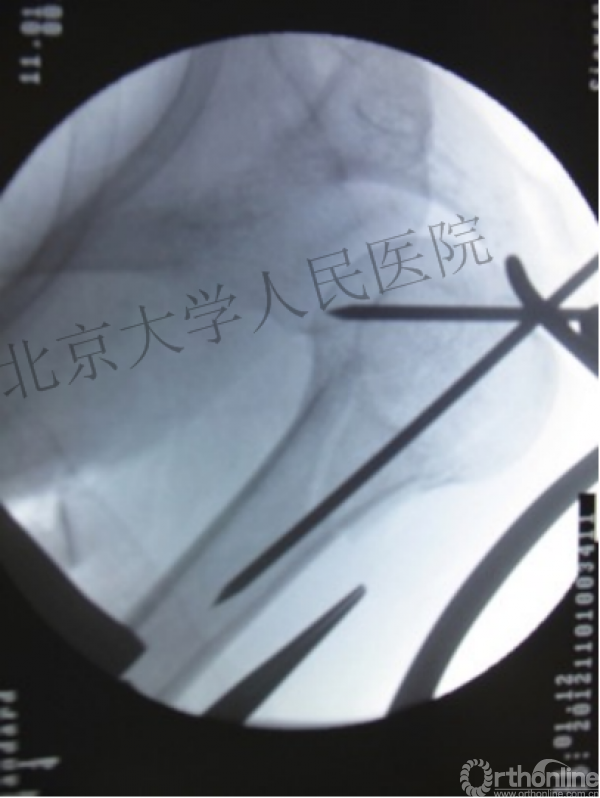

术中片